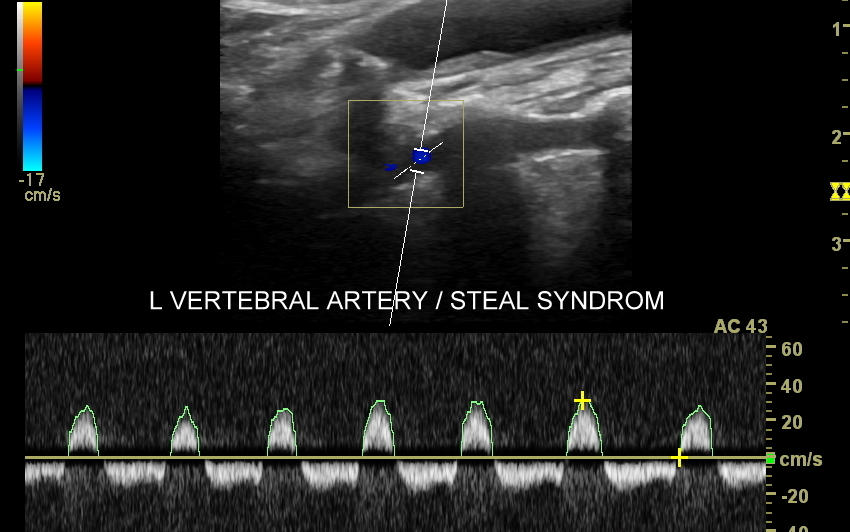

Choroby tętnic. Najczęstszą chorobą tętnic jest miażdżyca, która naturalnie i powoli rozwija się wraz z wiekiem, jednakże może ulec znacznemu przyspieszeniu i nasileniu pod wpływem takich czynników jak palenie papierosów, cukrzyca, zaburzenia lipidowe, czy nadciśnienie tętnicze. Rozwijająca się miażdżyca doprowadza do zwężeń naczyń tętniczych, a czasem nawet do ich zamknięcia wywołując objawy niedokrwienne. Przykładami ostrych chorób niedokrwiennych jest udar mózgowy oraz zawał serca. Z kolei przykładami przewlekłych zespołów związanych z miażdżycą są demencja, angina brzuszna i chromanie przestankowe. Inne choroby tętnic obejmują m. in. tętniaki, rozwarstwienia, zapalenia, czy zespoły podkradania, których cech poszukuje się w trakcie wykonywania badania USG Doppler tętnic.

Badanie USG Doppler tętnic szyjnych i kręgowych, określane również jako badanie USG tętnic dogłowowych, to najczęściej wykonywane badanie diagnostyczne w układzie tętniczym. Wynika to z faktu, iż wymienione naczynia doprowadzają krew do jednego z najważniejszych organów człowieka, tj. mózgu, a choroby lokalizujące się w tętnicach dogłowowych mogą być źródłem różnorodnych objawów neurologicznych począwszy od zaburzeń pamięci i widzenia, poprzez bóle i zawroty głowy, aż do zgonu na tle nagłego udaru niedokrwiennego. W trakcie standardowego badania USG tętnic dogłowowych oceniane po obu stronach są tętnice szyjne wspólne, wewnętrzne, zewnętrzne oraz tętnice kręgowe. Badanie niejednokrotnie rozszerza się o specjalistyczną ocenę USG łuku aorty, USG tętnic podobojczykowych, USG tętnic skroniowych, czy o badanie USG Doppler przezczaszkowy.

Badanie USG Doppler tętnic wewnątrzczaszkowych (ang. TCCD, transcranial color-coded Doppler), nazywane także Dopplerem przezczaszkowym jest naturalnym rozszerzeniem i uzupełnieniem badania dopplerowskiego tętnic dogłowowych zewnątrzczaszkowych. Badanie polega na obrazowaniu przy użyciu dedykowanej sondy poprzez tzw. okno skroniowe czaszki głównych naczyń tętniczych mózgu, tj. koła Willisa, tętnic mózgowych przednich, środkowych i tylnych po obu stronach. Badanie TCCD umożliwia wykrycie wybranych wewnątrzczaszkowych patologii naczyniowych takich jak tętniaki, malformacje naczyniowe, zwężenia i niedrożności poszczególnych tętnic mózgowych, spazm naczyniowy, a także pozwala na ocenę kierunku przepływy krwi w kole Willisa mózgu, co  jest przydatne przy diagnostyce zespołu podkradania lub w ocenie po przebyciu udaru mózgowego.

Badanie USG tętnic kończyn górnych górnych wykonywane jest ze wskazań podobnych jak w przypadku kończyn dolnych, a dodatkowo w ramach diagnostyki zespołu górnego otworu klatki piersiowej, zespołu podkradania z tętnicy kręgowej, zespołu Takayasu, czy olbrzymiokomórkowego zapalenia tętnic (choroba Hortona). Z kolei urazowymi patologiami naczyń dłoni i palców są niedrożności tętnic występujące w przebiegu klasycznej choroby wibracyjnej, czy uprawiania wspinaczki skałkowej.